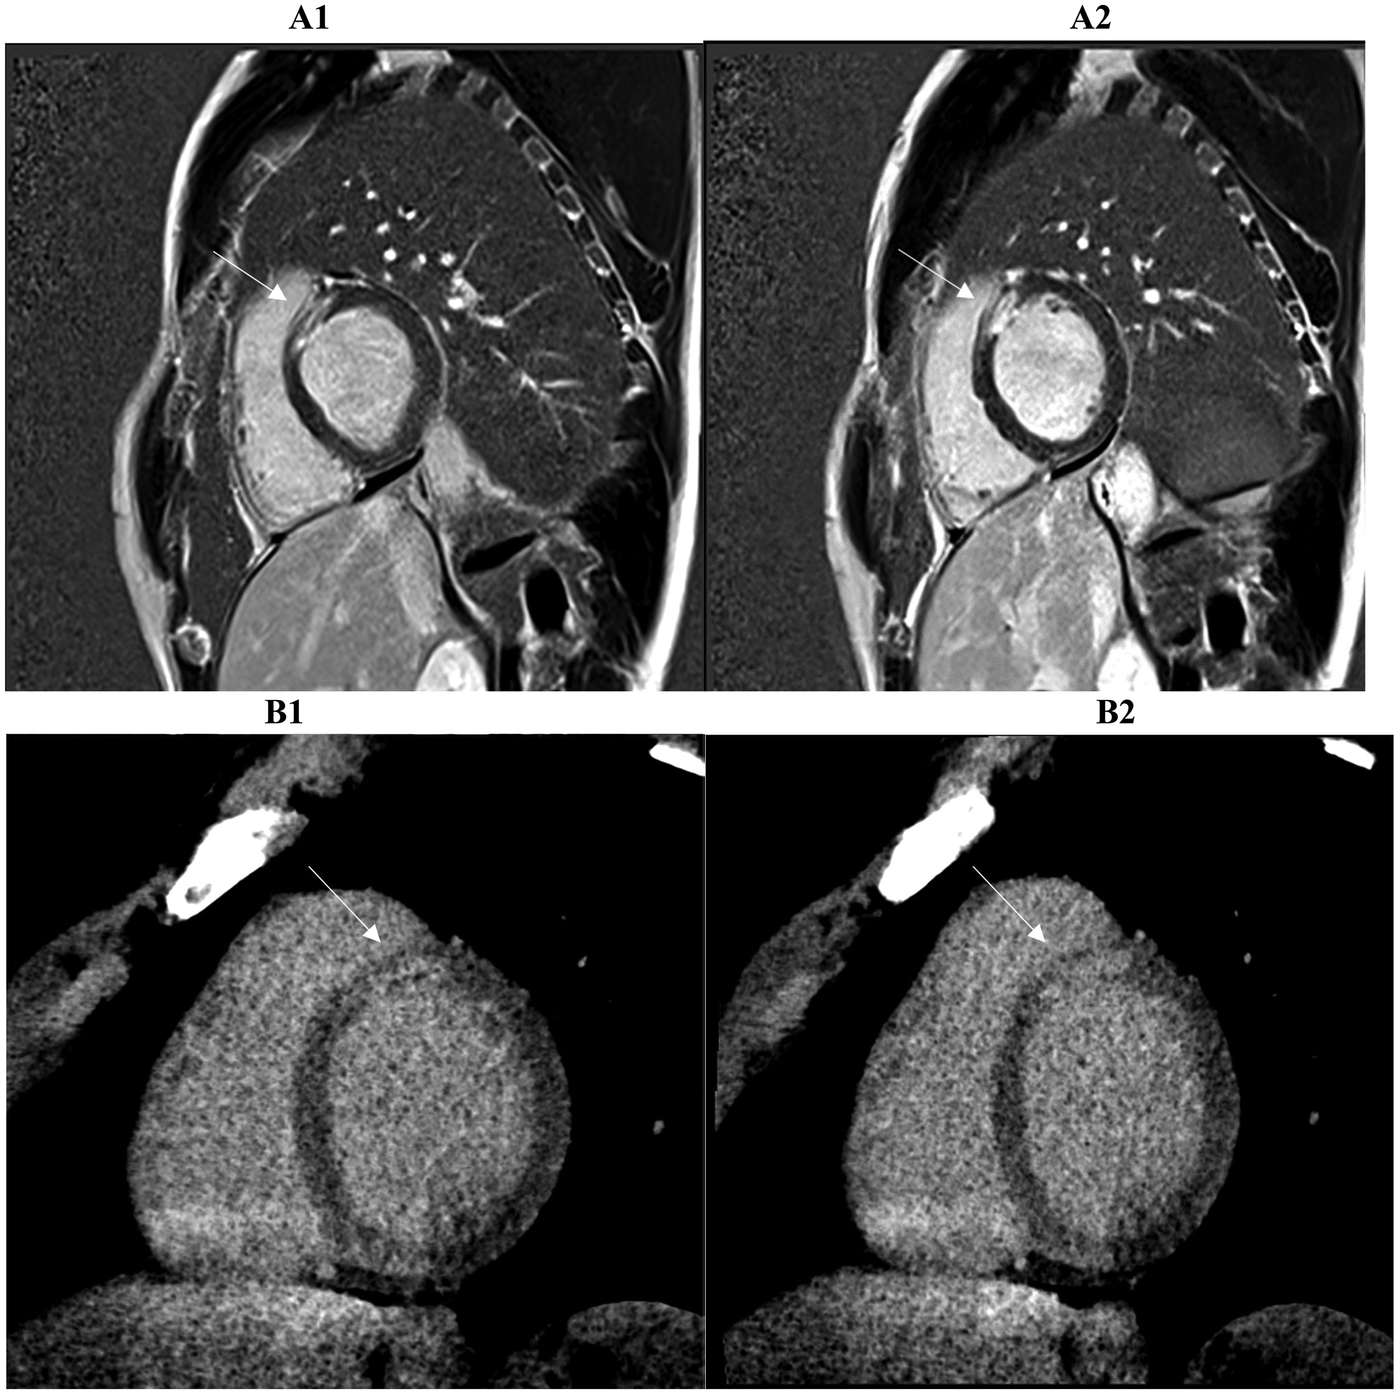

Figure 4

Two consecutive basal and mid-basal short-axis PSIR (phase sensitive inversion recovery) images (A1, A2) demonstrate transmural late gadolinium enhancement (LGE) in the territory of the anterior descending coronary artery (basal antero-septal wall, arrow) in a patient with suspected myocardial infarction with non-obstructed coronary arteries (MINOCA). The corresponding prior late iodine enhancement (LIE) images (B1, B2) show involvement of the same myocardial segments. The two imaging modalities exhibit 100% segmental concordance, defined as complete agreement on the presence or absence of enhancement within matching myocardial segments.

On a segment-by-segment comparison (Figure 3), LIE and LGE findings agreed in 17 of 21 patients (81 percent). Complete segmental concordance was present in all 8 MINOCA cases (Figure 4) and in 2 myocarditis cases. In the remaining myocarditis patients, concordance ranged from 25 to 83 percent of affected segments (Figure 5). Overall agreement (Table 3) was 100 percent in MINOCA and 15 percent in myocarditis (P < 0.001). Subendocardial enhancement correlated strongly with a final diagnosis of MINOCA (Spearman's ρ = 0.82, P < 0.001).